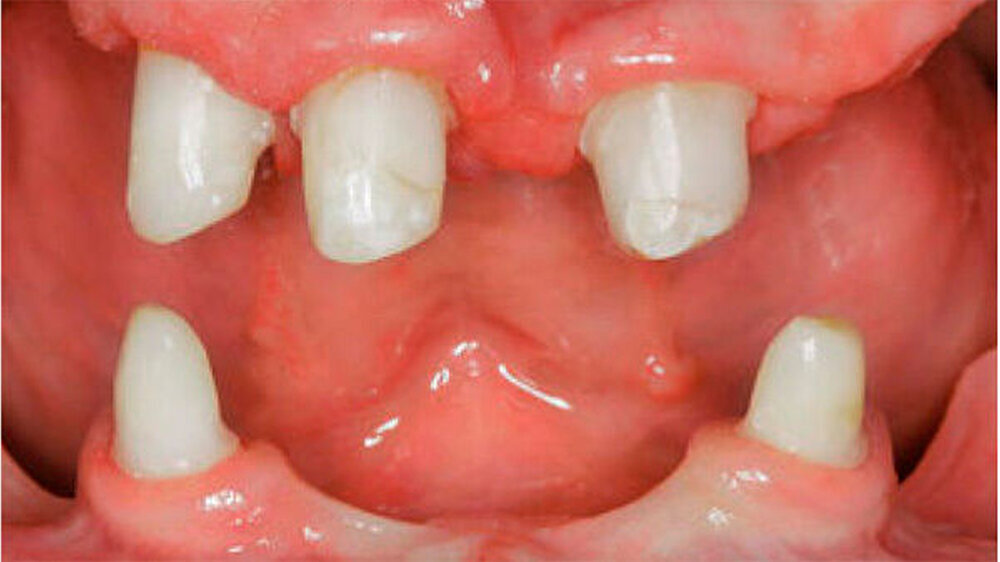

Der bei Behandlungsbeginn 14-jährige Patient war mit einer neun beziehungsweise fünfjährigen Prothese im Unter- beziehungsweise Oberkiefer versorgt (Abb. 2 und 3). Die angelegten Zapfenzähne 12, 11 und 21 waren bereits mehrfach konservierend restauriert und wiesen diverse Stellen mit Sekundärkaries auf. Die Kronenränder der Zähne 33 und 43 waren deutlich sondierbar. Der Kieferkamm im Unterkiefer war aufgrund der fehlenden Zahnanlagen sehr schmal (Abb. 4 bis 6). Die Panoramaschichtaufnahme zeigte das reduzierte vertikale Knochenangebot (Abb. 7). Da die Vitalerhaltung der wenigen Restzähne aufgrund des jungen Alters des Patienten unbedingt anzustreben war, wurde als Behandlungsziel im Ober- und Unterkiefer eine Versorgung mit Hybridprothesen, retiniert auf Teleskopkronen, festgelegt.

Bei dieser bei Behandlungsbeginn 16-jährigen Patientin waren seit Geburt nur die beiden ersten Molaren im Oberkiefer ausgebildet. Die Folge waren schmale und niedrige Alveolarkämme mit einem flachen Gaumengewölbe (Abb. 16 und 17). Die röntgenologische Abbildung bestätigte das geringe vertikale Knochenangebot. Eine Formanomalie der Zahnwurzeln ließ auf taurodonte Molaren schließen. Beide Molaren wiesen ausgedehnte kariöse Läsionen auf (Abb. 18).